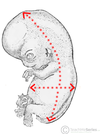

orange: flexion

blue: extension